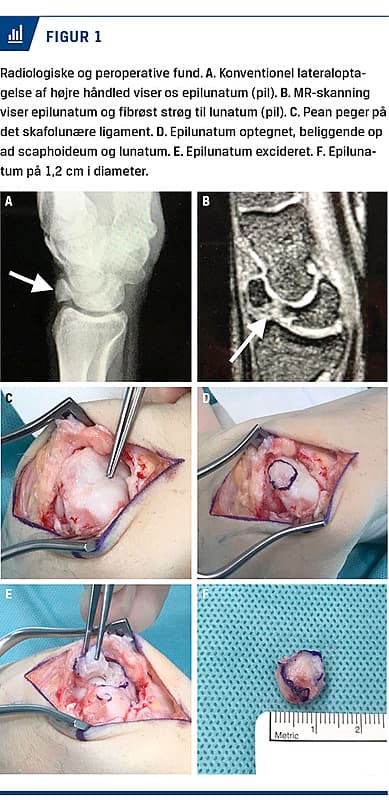

En konventionel lateral røntgenoptagelse viste en accessorisk knoglekerne dorsalt for os lunatum. Ved en MR-skanning påvistes en fibrøs forbindelse imellem knoglekernen og os lunatum – en os epilunatum. Beliggenheden var i nær relation til det skafolunære (SL) ligament, som på MR-skanningen kunne ses at være intakt.

Patienten blev tilbudt kirurgi. Igennem en dorsal adgang til håndleddet blev os epilunatum lokaliseret. Peroperativt kunne man tydeligt se, at epilunatum kolliderede mod radius’ dorsale afgrænsning og forhindrede ekstension af håndleddet. Epilunatum blev frilagt og fjernet in toto, uden at SL-ligamentet blev beskadiget (Figur 1). Peroperativt kunne håndleddet passivt ekstenderes til 60° og flekteres fuldt. SL-ligamentet blev fundet intakt efter excisionen. Ledkapslen og huden blev lukket lagvist. En dorsal gipsskinne blev anlagt og skulle bæres i tre uger for at give ledkapslen ro til heling. Herefter påbegyndte patienten ergoterapi for at træne bevægeligheden.